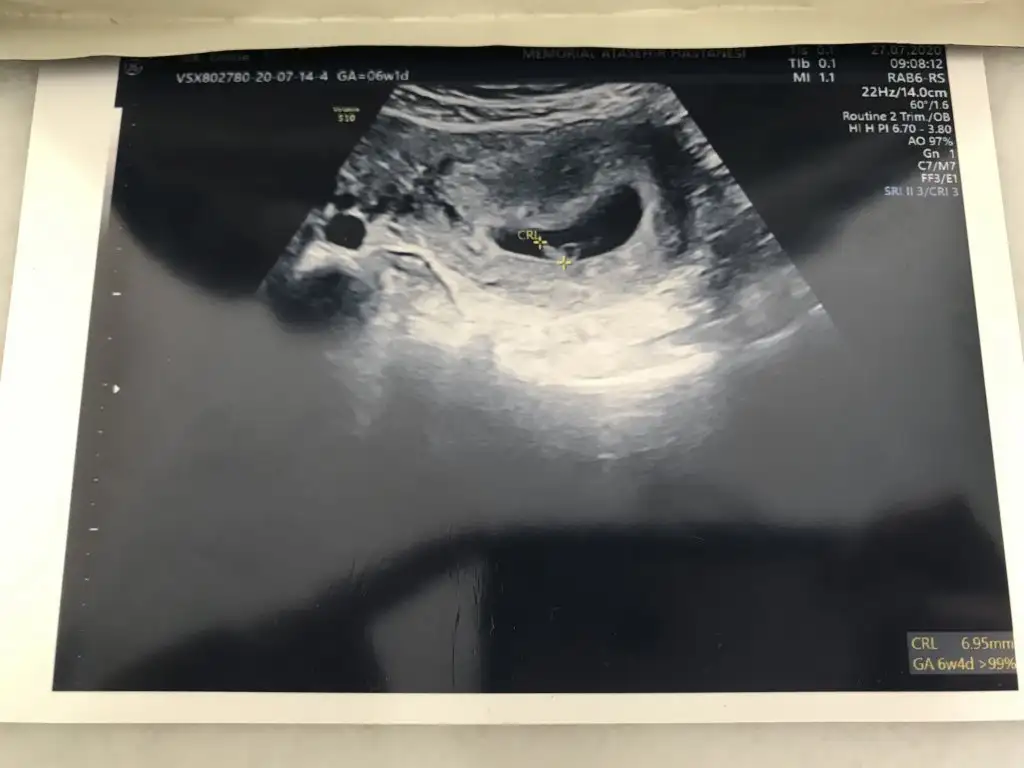

Karından ise Erkek buna göre en iyi 11 12 13 haftalar olmalı

Evet vajinelden ise erkek ama en iyi 11 12 13 haftalar olmalıVajinal bakildi canim farkediyor mu?

Evet karından 12. hafta tekrar rahatsız ederim o zaman çok teşekkür ederimKarından ise Erkek buna göre en iyi 11 12 13 haftalar olmalı